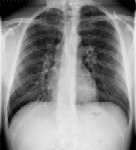

Συγκρίνετε το αποτέλεσμα ρύθμισης φωτεινότητας και ρύθμισης φωτεινότητας πολλαπλών κλιμάκων σε μια εικόνα θώρακα CR:

Μια εικόνα με αυξημένη αντίθεση που χρησιμοποιεί ρύθμιση φωτεινότητας πολλαπλών κλιμάκων δεν εμφανίζει αποκοπή

Ρύθμιση φωτεινότητας πολλαπλών κλιμάκων